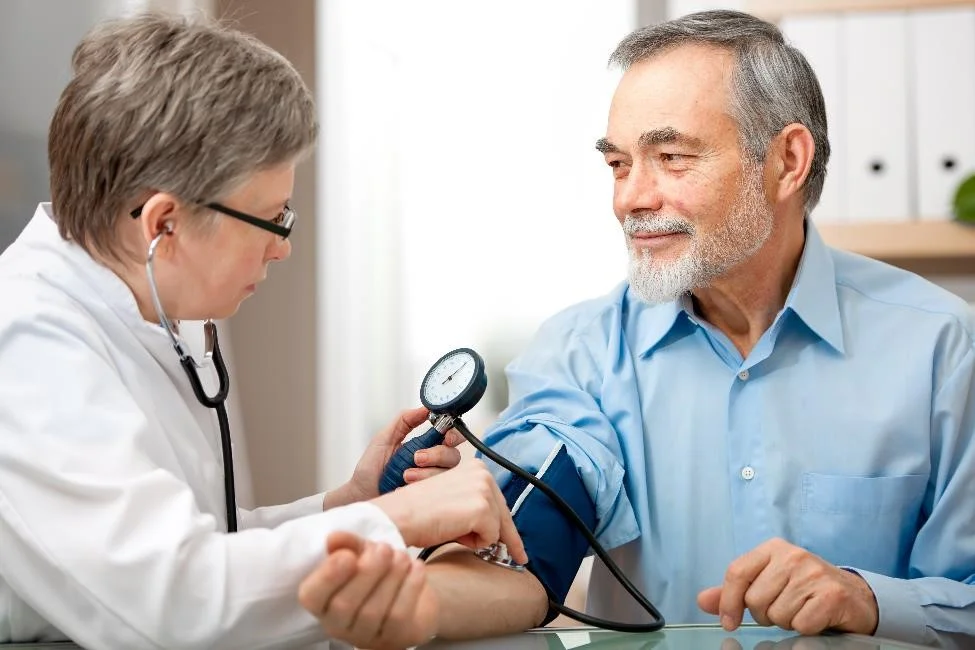

Hyper & Renal Care

Comprehensive, specialized medical care for patients with advanced or complex kidney diseases and conditions.